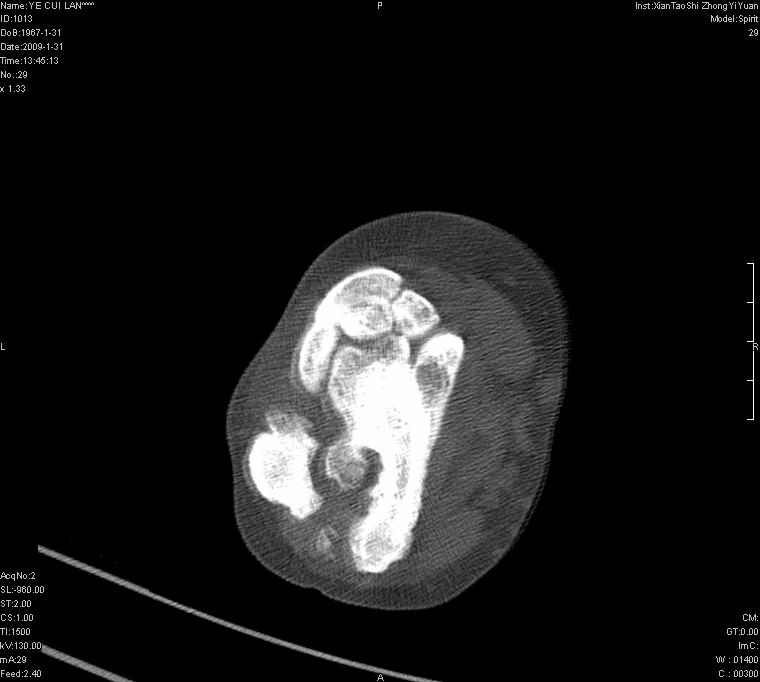

以下是引用王明发在2009-2-9 11:53:00的发言:[br]支持夏科氏关节,必要时行脊髓mri检查 [br]夏科氏关节是指由于某些神经系统疾病引起的关节病变,也被称为神经性关节炎。常见病因有脊髓痨、脊髓空洞症等。原发的神经病变可以造成关节深部感觉障碍,对于关节的震荡、磨损、挤压、劳倦不能察觉因而也不能自主地保护和避免,而神经营养障碍又可使修复能力低下,使病人在无感觉状态下造成了关节软骨的磨损和破坏,关节囊和韧带松弛无力,易形成关节脱位和连枷关节。关节面的破坏和骨赘的脱落变成关节内游离体。关节外形饱满肿胀,内有出血和渗出。这种病早期并无疼痛,不易被病人重视,仅表现为关节肿胀、无力、活动过度、动摇不稳。关节肿胀、无痛、活动范围超常是本病的重要特征。x光片可见有关节骨端广泛破坏、硬化或呈奇异形态,骨赘形成,关节间隙不规则或增宽,周围软组织钙化、关节内游离体、骨碎片等。结合x光片及临床症状,病人又有神经系统原发病症,即可确诊

以下是引用hhcckk在2009-2-9 14:31:00的发言:[br]夏科关节的六大表现[br]1.关节软组织肿胀。[br]2.关节的脱位与半脱位。[br]3.关节内的游离体。[br]4.关节面硬化,新骨形成。[br]5.骨质萎缩与破坏。[br]6.关节结构的紊乱。[br]加上患者无明显疼痛,诊断的把握性比较大